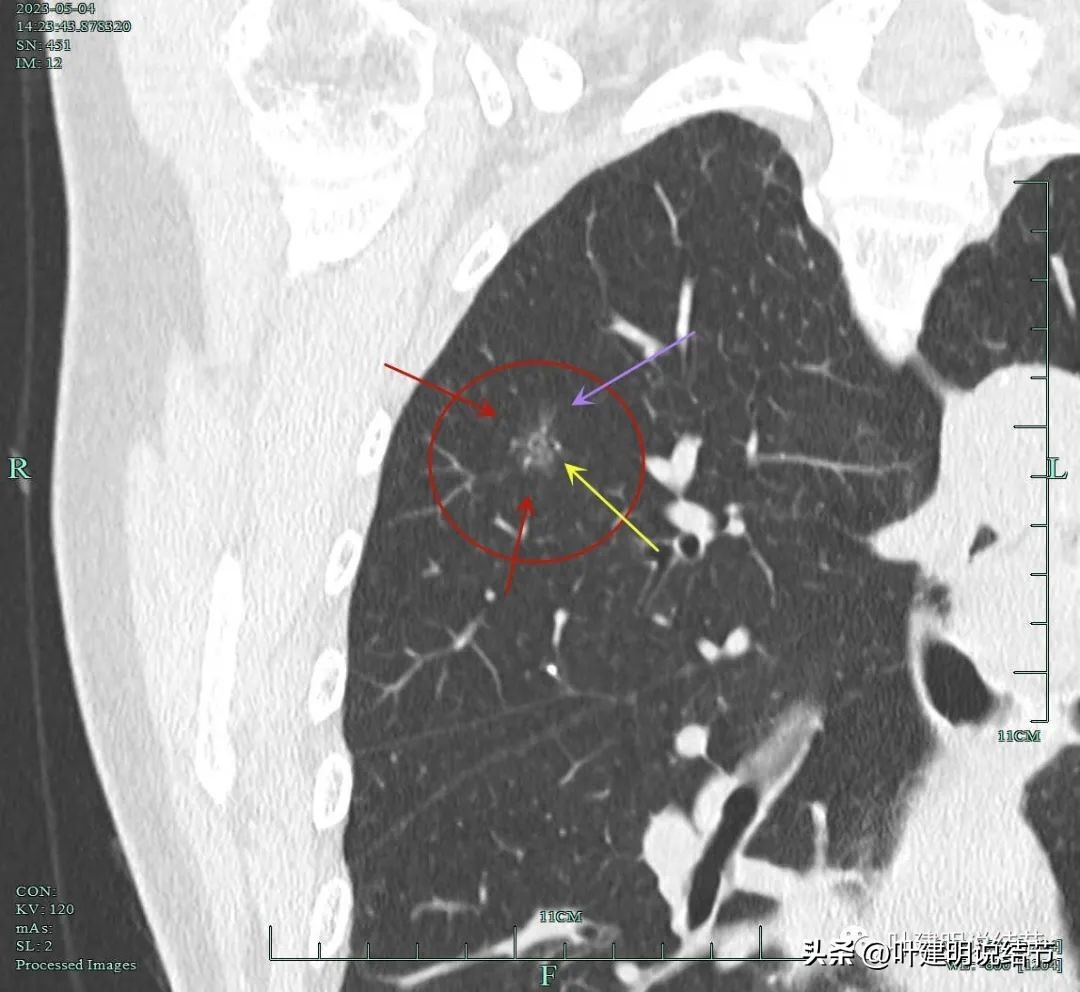

非薄层扫描显露右上叶略显模糊的磨玻璃结节,中间有小空泡的样子,边缘不平显得有毛刺样征,密度不均匀。

薄层显示病灶磨玻璃密度,内部有血管穿行,灶内有小空泡的样子,整体边缘轮廓较清。

灶内穿行的血管有异常增粗,且显得毛糙。灶内空泡样征是扩张的细支气管;表面不平,似有浅分叶的样子。磨玻璃部分密度较低。

上图显示血管进入病灶,进入后似乎就散掉了。

靶扫描重建发现病灶内部穿行血管毛糙,细支气管扩张,边缘毛刺样征。

灶内走行的血管模糊、异常增粗与毛糙。病灶总体轮廓较清,磨玻璃部分密度较低。

上图显示明显的血管弯征。而且磨玻璃病灶密度欠均匀。

病灶分叶、细支气管扩张,微小血管进入;整体轮廓较清。

上图这个视角清楚显示灶内的空泡征是扩张的细支气管。而且灶外细些,灶内更远离肺门,反而扩张,说明病灶有牵拉力呀!

边缘有毛刺征,灶内密度欠均。